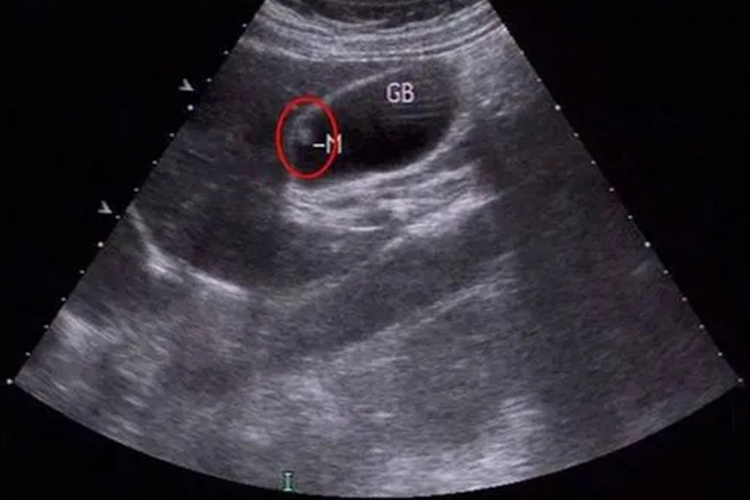

胆囊息肉样病变什么意思

胆囊息肉样病变通常不严重以下是关于胆囊息肉样病变的详细解答1 定义与误解 胆囊息肉样病变是胆囊内隆起性病变的总称,易引起误解,但与癌变是完全不同的概念2 分类与性质 根据性质,胆囊息肉可分为胆固醇性息肉腺瘤性息肉炎性...